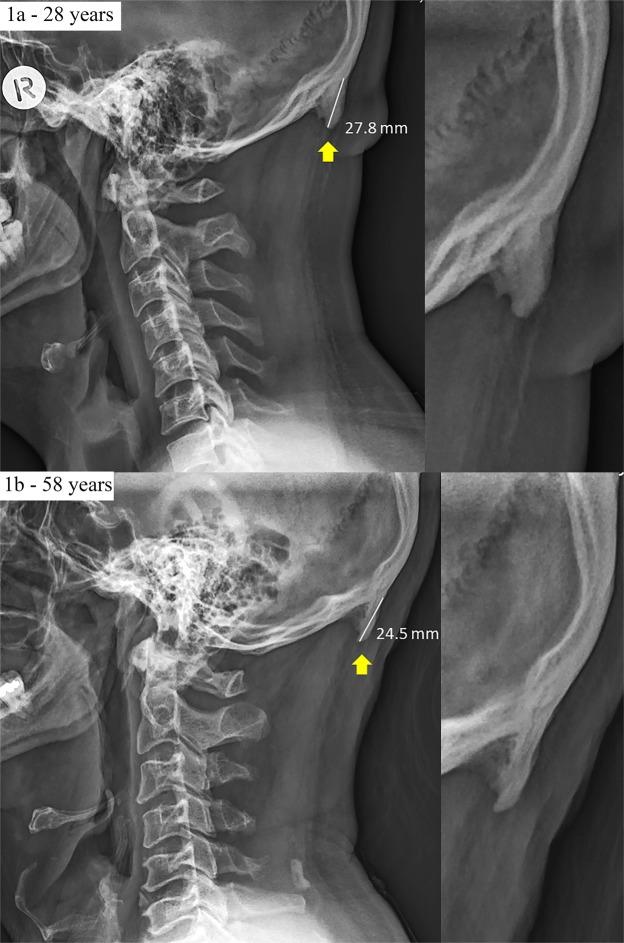

Prominent exostosis projecting from the occipital squama more substantial and prevalent in young adult than older age groups.

Recently we reported the development of prominent exostosis young adults' skulls (41%; 10-31 mm) emanating from the external occipital protuberance (EOP). These findings contrast existing reports that large enthesophytes are not seen in young adults. Here we show that a combination sex, the degree of forward head protraction (FHP) and age predicted the presence of enlarged EOP (EEOP) (n = 1200, age 18-86). While being a male and increased FHP had a positive effect on prominent exostosis, paradoxically, increase in age was linked to a decrease in enthesophyte size. Our latter findings provide a conundrum, as the frequency and severity of degenerative skeletal features in humans are associated typically with aging. Our findings and the literature provide evidence that mechanical load plays a vital role in the development and maintenance of the enthesis (insertion) and draws a direct link between aberrant loading of the enthesis and related pathologies. We hypothesize EEOP may be linked to sustained aberrant postures associated with the emergence and extensive use of hand-held contemporary technologies, such as smartphones and tablets. Our findings raise a concern about the future musculoskeletal health of the young adult population and reinforce the need for prevention intervention through posture improvement education.

最近,我们报道了年轻人颅骨(41%;10-31mm)外枕外隆凸(EOP)出现明显外生骨赘的情况。这些发现与现有的报告相矛盾,即年轻人的大附着点骨赘没有被发现。在这里,我们展示了性别、头部前伸程度(FHP)和年龄的组合可以预测 EOP 增大(EEOP)的存在(n=1200,年龄 18-86 岁)。虽然男性和 FHP 增加对明显外生骨赘有积极影响,但矛盾的是,年龄的增加与附着点骨赘的大小减少有关。我们的后一个发现提出了一个难题,因为在人类中,骨骼退行性特征的频率和严重程度通常与衰老有关。我们的发现和文献提供了证据,证明机械负荷在附着点(插入)的发育和维持中起着至关重要的作用,并在附着点的异常负荷和相关病变之间建立了直接联系。我们假设 EEOP 可能与与手持现代技术(如智能手机和平板电脑)的出现和广泛使用相关的持续异常姿势有关。我们的发现引起了对年轻成年人未来肌肉骨骼健康的关注,并强调需要通过改善姿势教育进行预防干预。